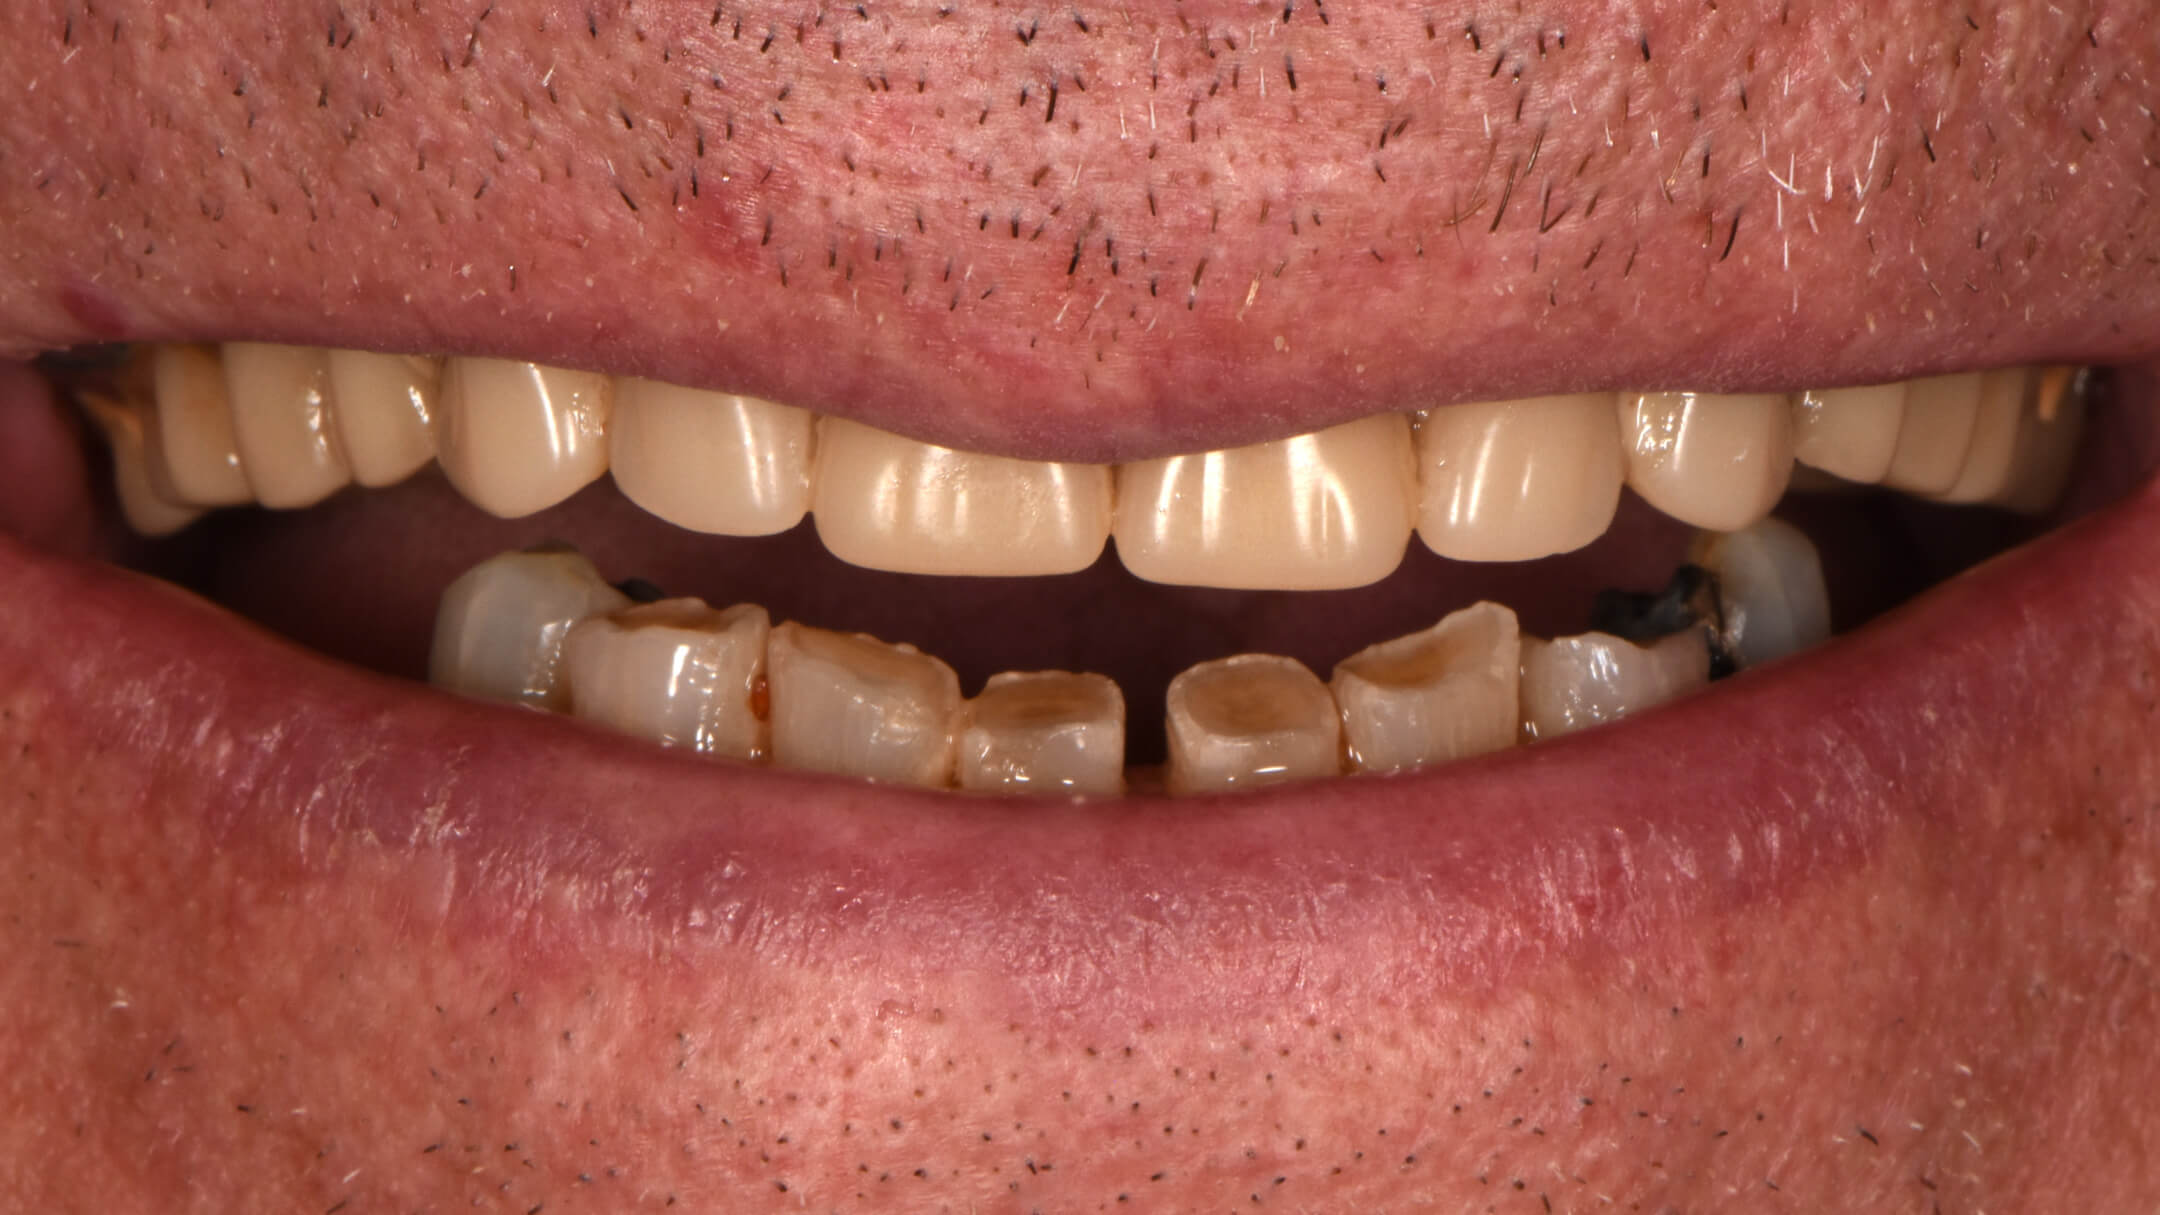

Dental Implants

Before